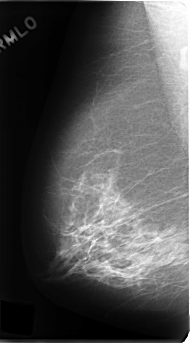

C_0191_1.RIGHT_MLO

RIGHT_MLO LINES 4808 PIXELS_PER_LINE 2648 BITS_PER_PIXEL 12 RESOLUTION 50 NON_OVERLAY